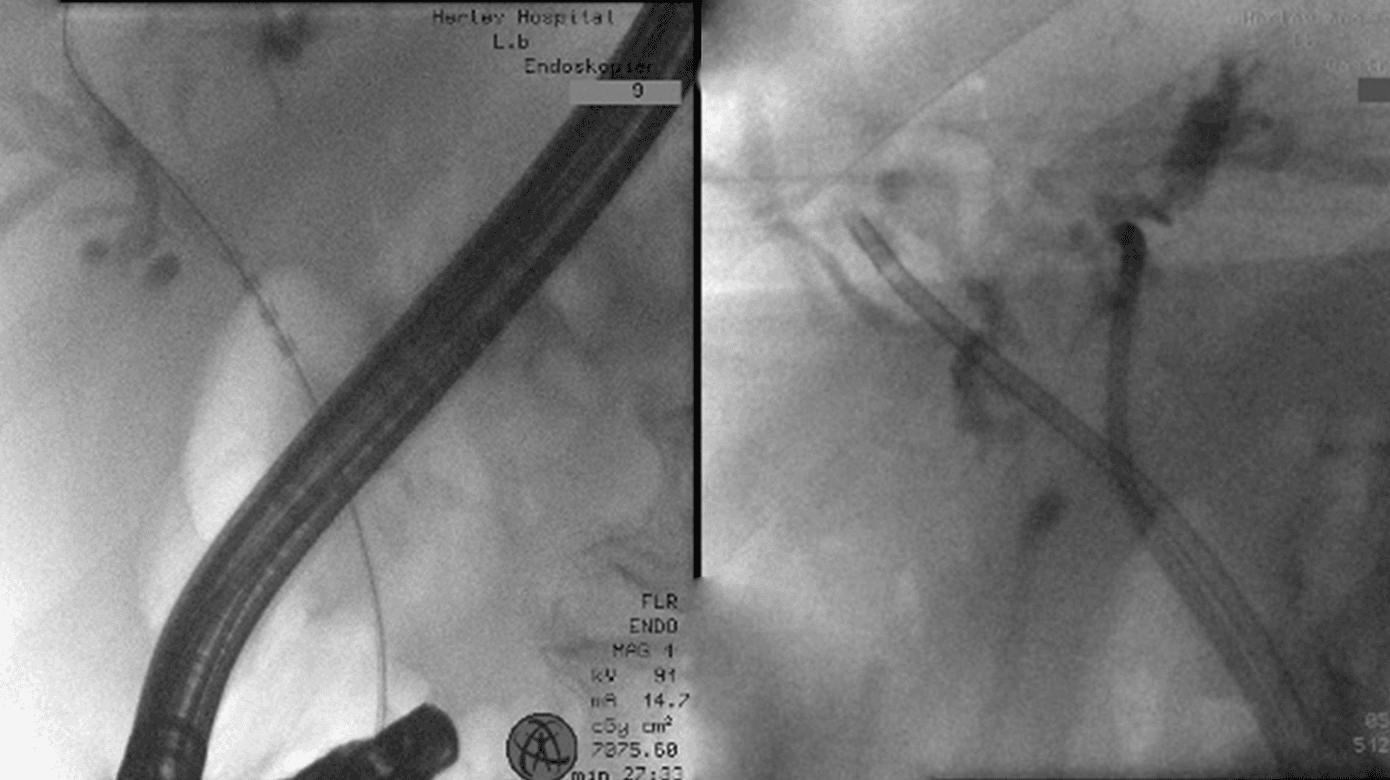

Der blev initialt foretaget endoluminal RFA af tumorvæv ved bifurkaturen, idet man anvendte en probe på 18 mm/7 Fr, 10 W i 2 min, hvorefter der igen kunne opnås adgang til venstre ductus hepaticus, som tidligere havde været okkluderet. Ablationen fortsatte ukompliceret i venstre galdetræ, og til slut blev der anlagt stents på hhv. 12 cm/7 Fr og 12 cm/8,5 Fr i ductus hepaticus sinister og ductus hepaticus dexter, som begge fungerede med galdeafløb.